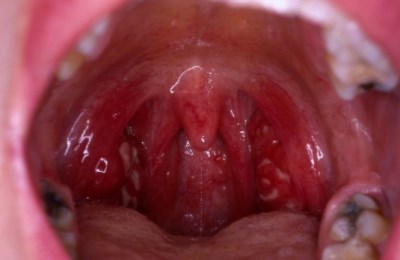

Выделяют следующие формы заболевания:

- Катаральная.

- Фолликулярная.

- Лакунарная.

- Флегмонозная.

- Язвенно-некротическая.

- Ангина Симоновского-Плаута-Венсана.

Наиболее частыми симптомами ангины является боль при глотании, которая с течением времени становится постоянной, высокая температура тела, признаки общей интоксикации, также возможно появление герпетической сыпи.